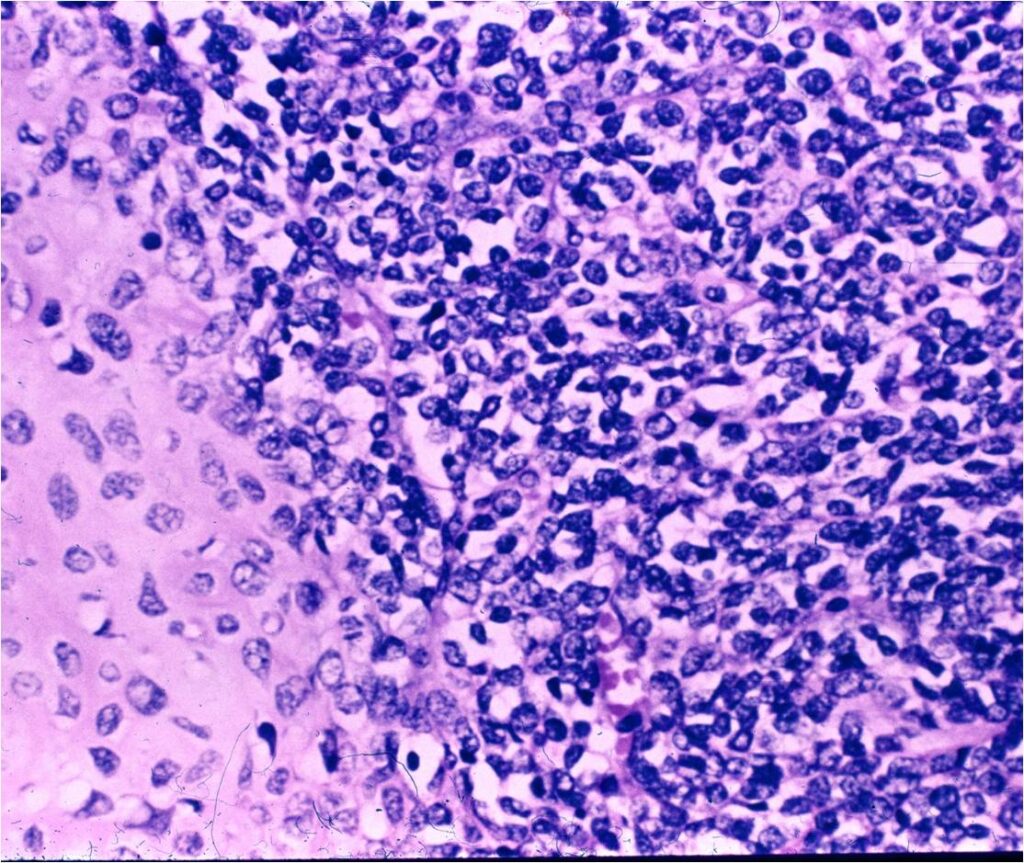

- Comprised primarily of noncartilaginous small, round, oval, or spindle shaped cells with islands of malignant cartilage dispersed throughout noncartilaginous component of tumor

- Low grade islands of cartilage scattered throughout the mesenchymal cells

- Usually only a small part of lesion

- Cytologically low grade

- Usually sharply demarcated from surrounding stroma

- Lesions are vascular and often have large, anastomosing vessels that impart hemangiopericytoma-like pattern